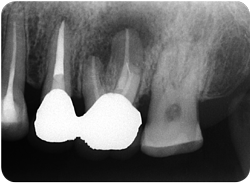

図❶ 初診時のデンタルX線画像

パノラマX線写真:6尖部に破折リーマーと考えられる不透過像あり。同部に、根尖を含むφ4㎜程度の透過像を認める。